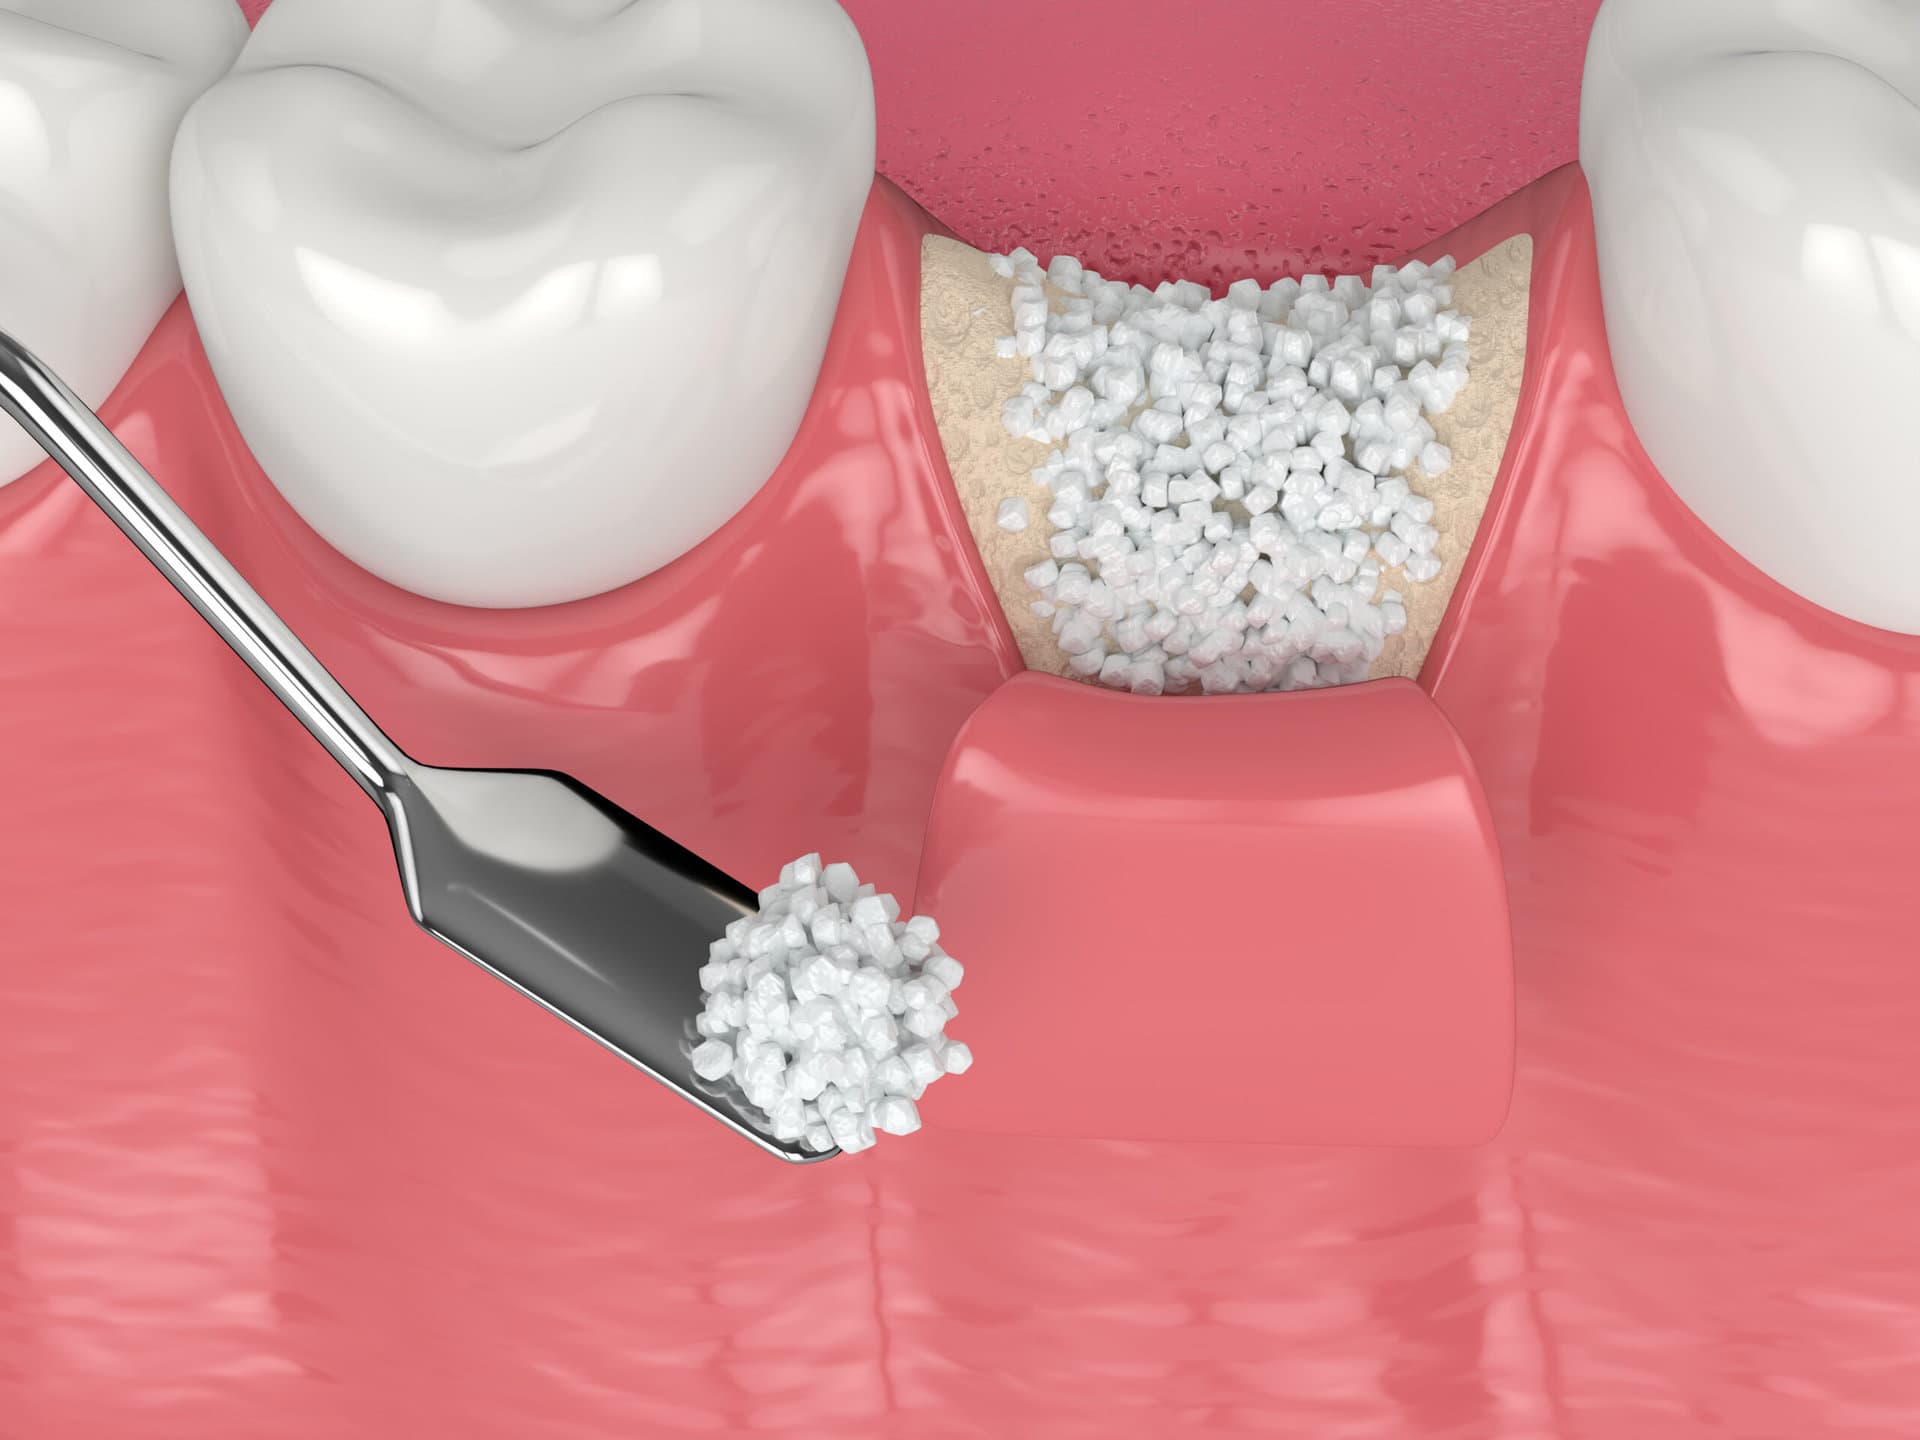

Early-stage gum disease (gingivitis) can often be managed with a professional cleaning and improved home care. More advanced disease may require scaling and root planing, surgical pocket reduction, or regenerative procedures. The sooner you come in, the more options are available — and the more of your natural teeth we can preserve.